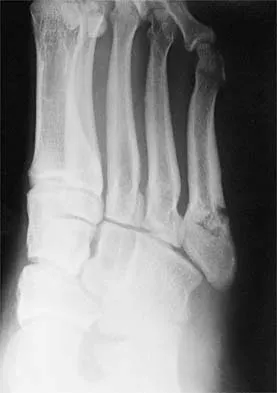

Figures 33a and 33b show the radiographs of a 10-year-old girl who reports a 4-month history of medial foot pain after she was kicked while playing soccer. The pain is worse with activity and partially relieved by rest. Examination reveals tenderness directly over a prominent navicular tuberosity. Management should consist of

An accessory tarsal navicular is located at the medial tuberosity of the navicular bone. Nearly all children and adolescents who have a symptomatic accessory tarsal navicular bone become asymptomatic when they reach skeletal maturity. Initial management should include activity restrictions, shoe modification to avoid pressure over the prominent navicular, and non-narcotic analgesics. Although anecdotal, the use of arch supports may be helpful. When pain is refractory to these methods, a short period of cast immobilization may be useful. Surgery should be reserved for patients who have disabling symptoms despite a prolonged period of nonsurgical management. When surgery is indicated, simple excision of the accessory navicular is recommended. Sella EJ, Lawson JP, Ogden JA: The accessory navicular synchondrosis. Clin Orthop 1986;209:280-285.